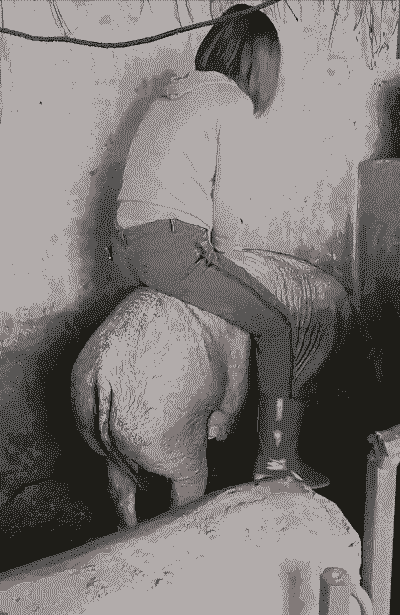

人工剥离:如果自然排出困难,可以消毒后用手伸到子宫内,将胎衣和宫壁剥离,人工将胎盘取出。